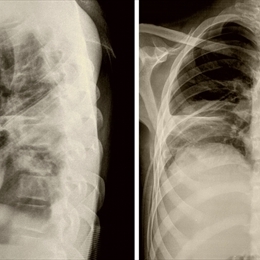

COVID-19, herhangi bir bulgu vermeyen enfeksiyondan, hafif üst solunum yolu hastalığına, akciğer enfeksiyonuna, şiddetli solunum sıkıntısına ve ölüme kadar varabilen geniş bir yelpazede kişileri etkileyebilmektedir.

•Solunum sıkıntısı,

•Göğüs ağrısı veya göğüste gerim hissi,